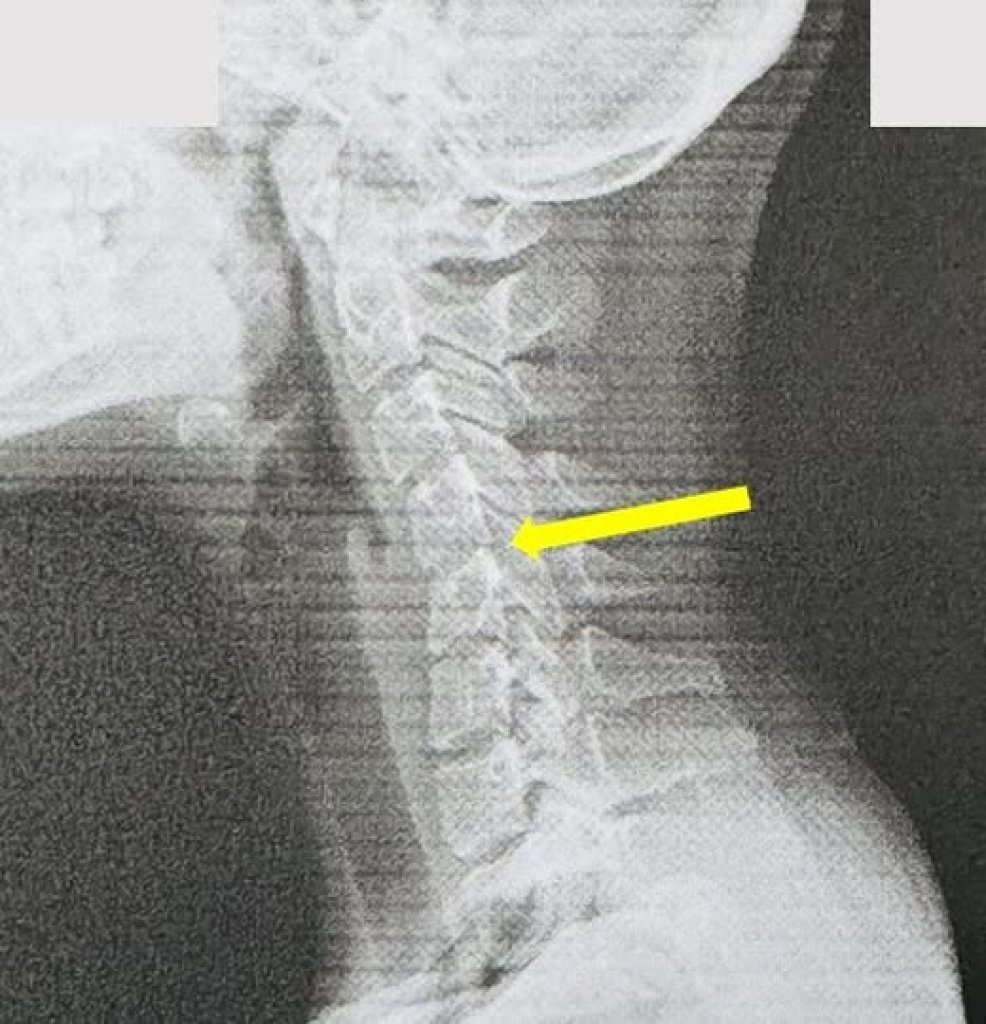

合作媒體20歲女大生長期滑手機,頸椎提早老化 宛如60歲老人圖說:員榮葉宗勳醫師解釋 一般低頭族滑手機時的情況,頸椎如承受27公斤的重量。【賴傳媒、記者爆料網/曾厚銘/彰化報導】 …2025-09-10